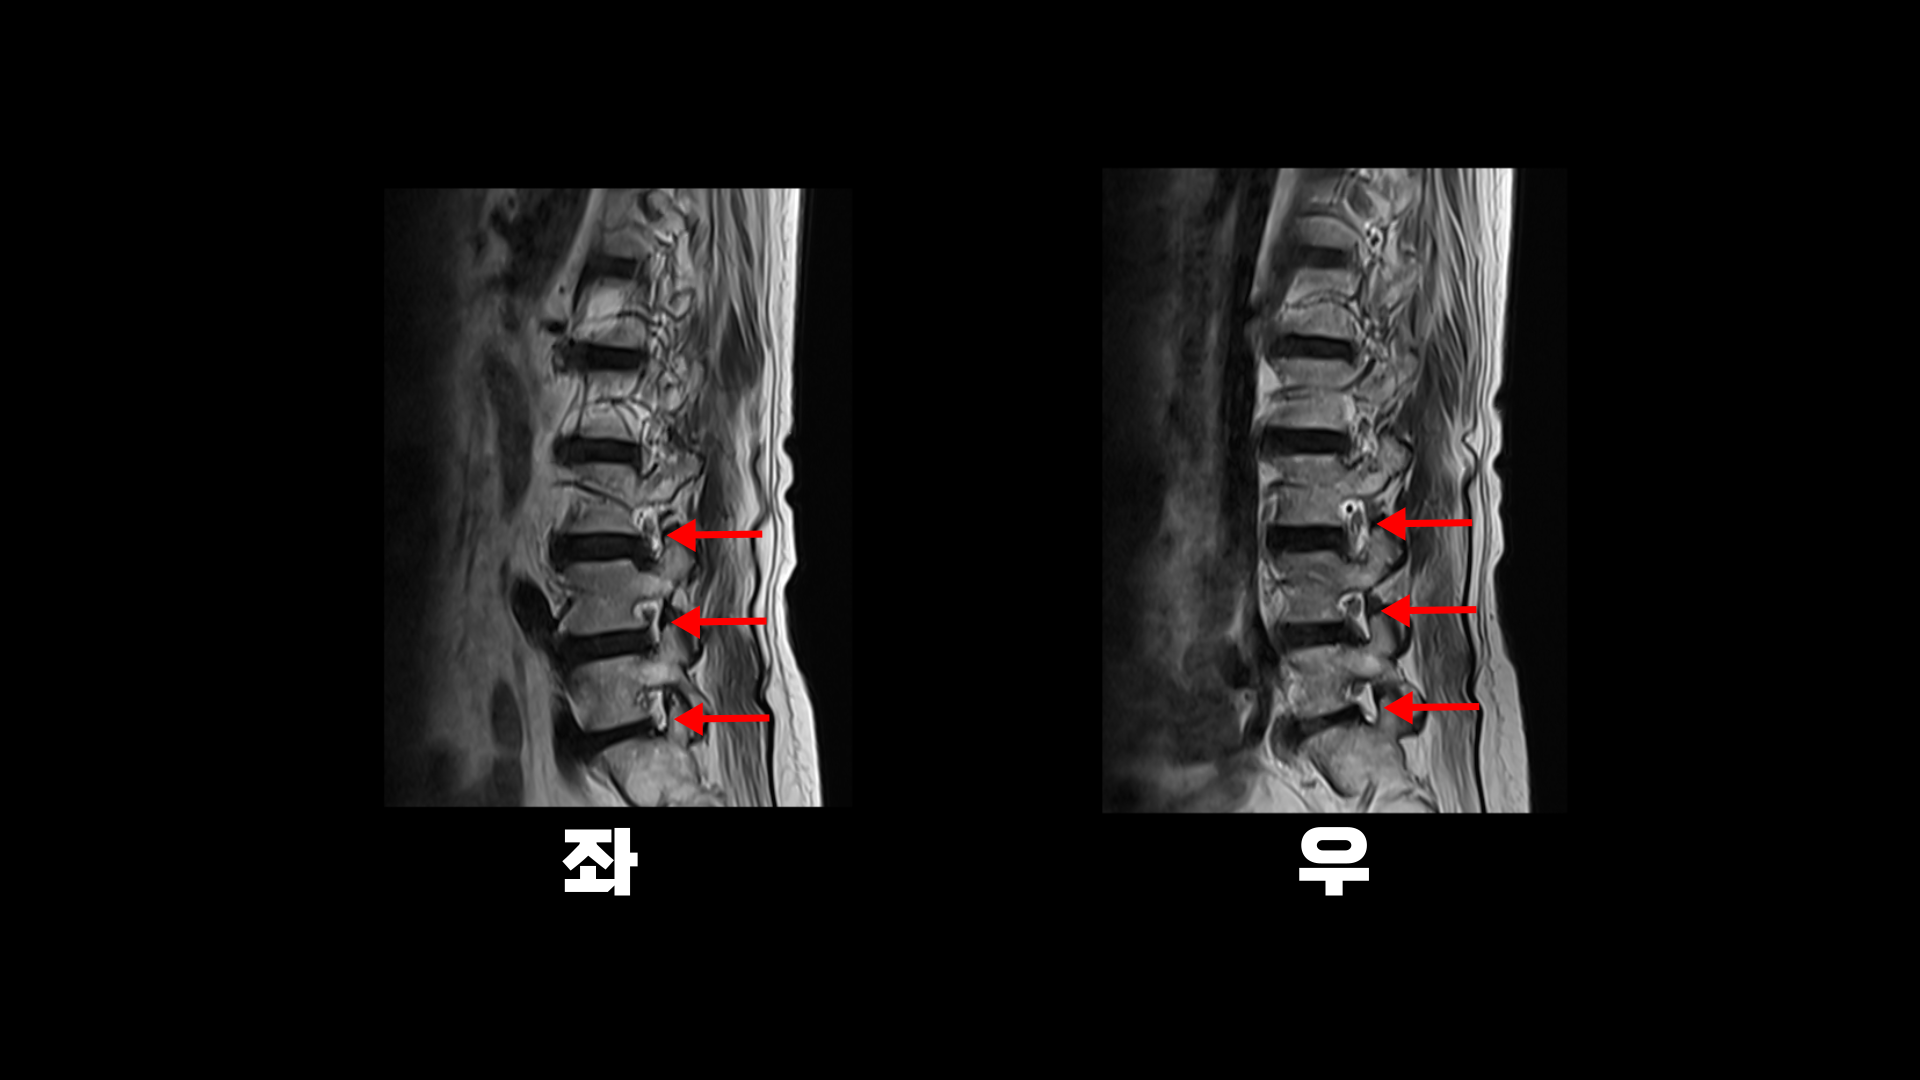

이분 MRI를 보면 74세의 연세답게 여러 마디의 퇴행성 디스크가 있습니다. 하지만 심하지 않습니다.

3번 4번에 황색 인대가 조금 두꺼워진 중심성 협착이 보이지만 역시 심하지는 않습니다.

좌우의 신경구멍도 막힌 곳이 없습니다.